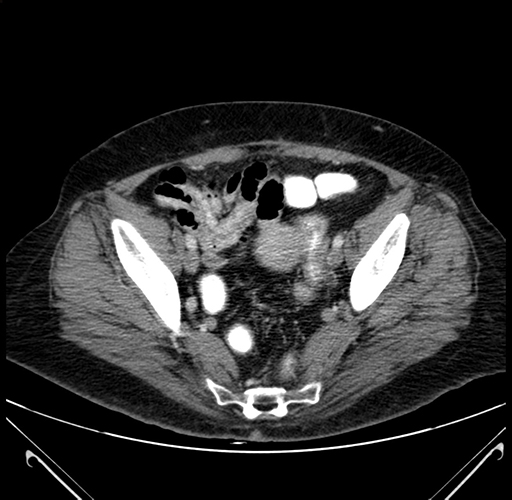

Pre-Chemo: Axial Venous

Axial Venous